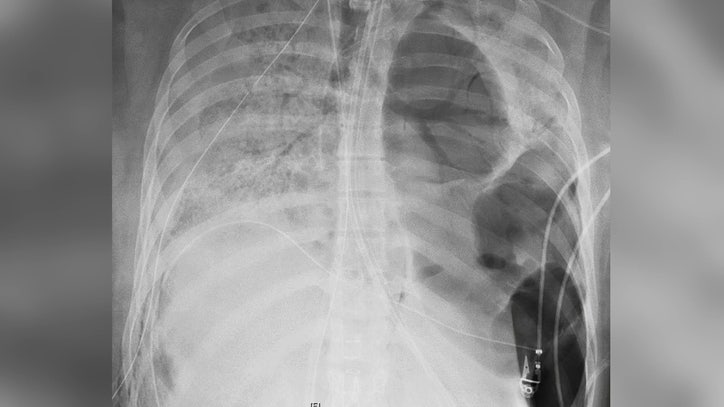

Coronavirus What X Rays And Ct Scans Reveal About How Covid 19 Kills Science Tech News Sky News

Chest Ct Shows Covid 19 Damage To The Lungs